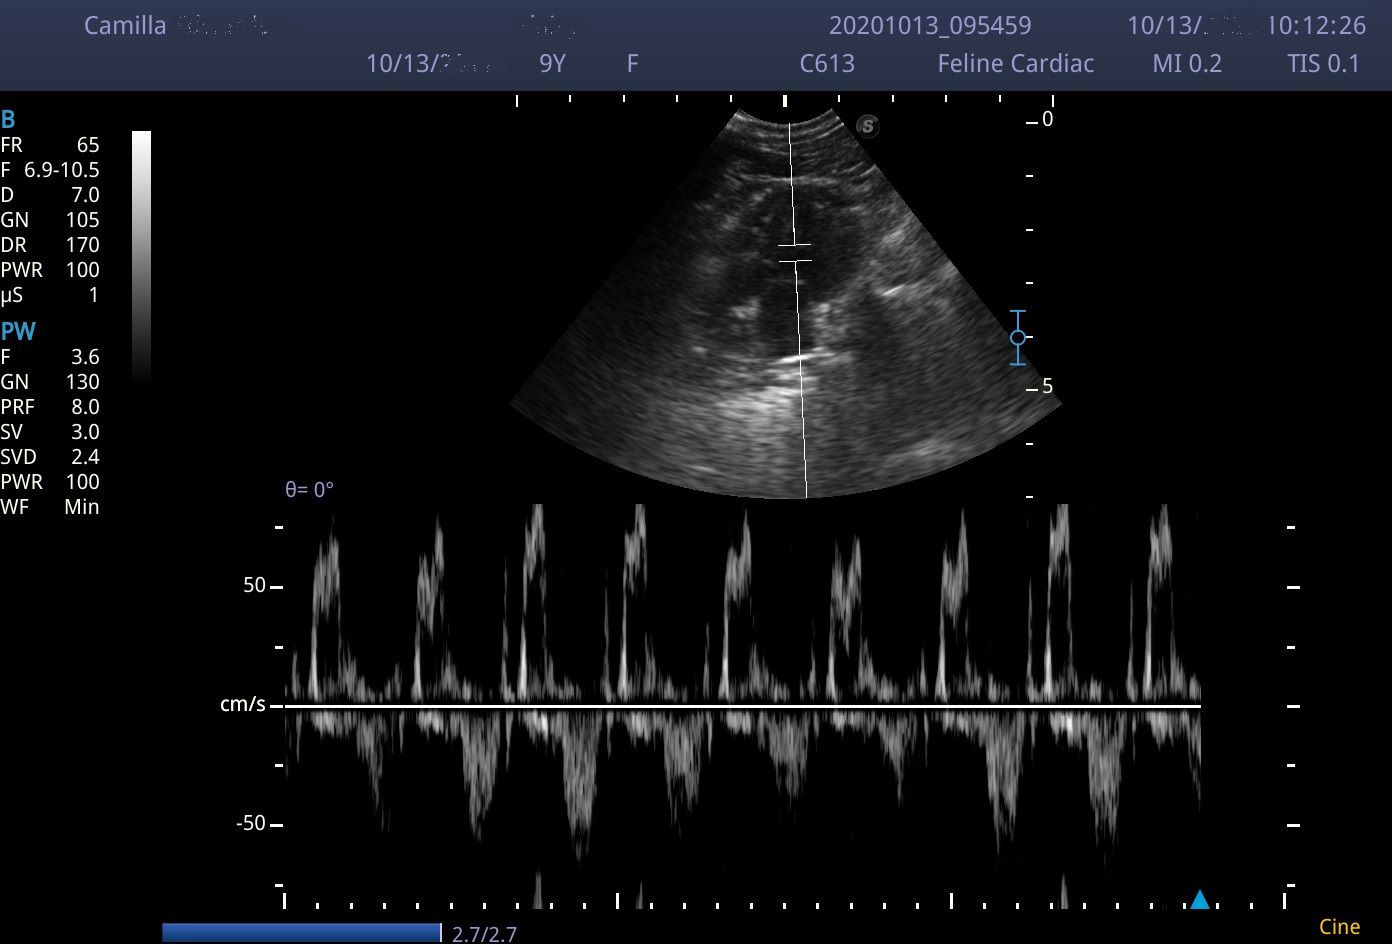

I scanned with the microconvex C613 probe (4-13MHz) and the linear L741 (4-6MHz). Although the linear probe gives great images, the 4.5cm footprint does make maneuverability around a small cat abdomen a little tricky. I used the microconvex probe was used in a few dogs and cardiac cases and it held up well.

Images from the E2V